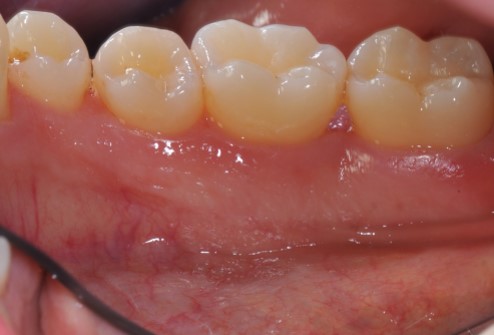

Radiographic view before periodontal regenerative therapy with Straumann® Emdogain®. A deep intrabony defect appeared mesially and distally on the left mandibular first premolar. Pre-surgical probing measured 8 mm. The defect morphology presented as well-contained.